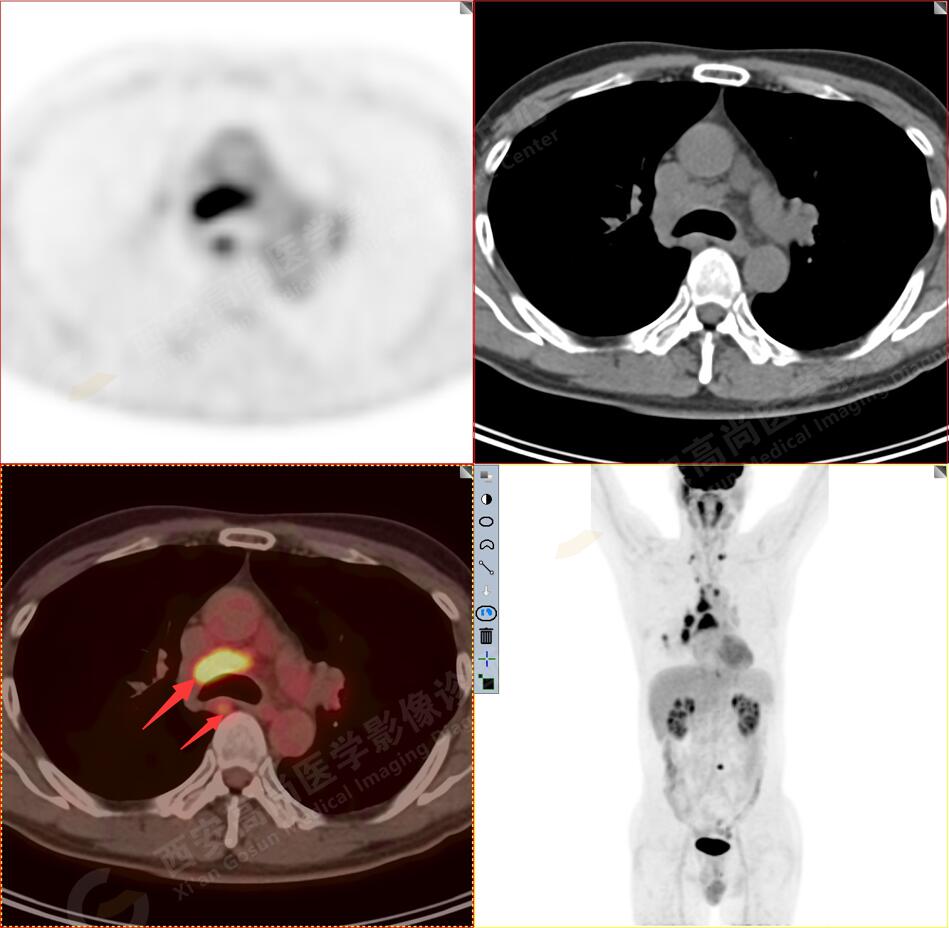

2.以下為全身多發(fā)轉移灶

2.雙肺多發(fā)高密度小結節(jié)灶(最大徑約0.7cm),部分較大結節(jié)呈FDG代謝略增高,均考慮為轉移性病變。

4.右后胸膜輕度增厚,形成多個條狀軟組織病變,呈FDG代謝輕度異常增高,考慮為轉移性病變;右側胸腔微量積液。